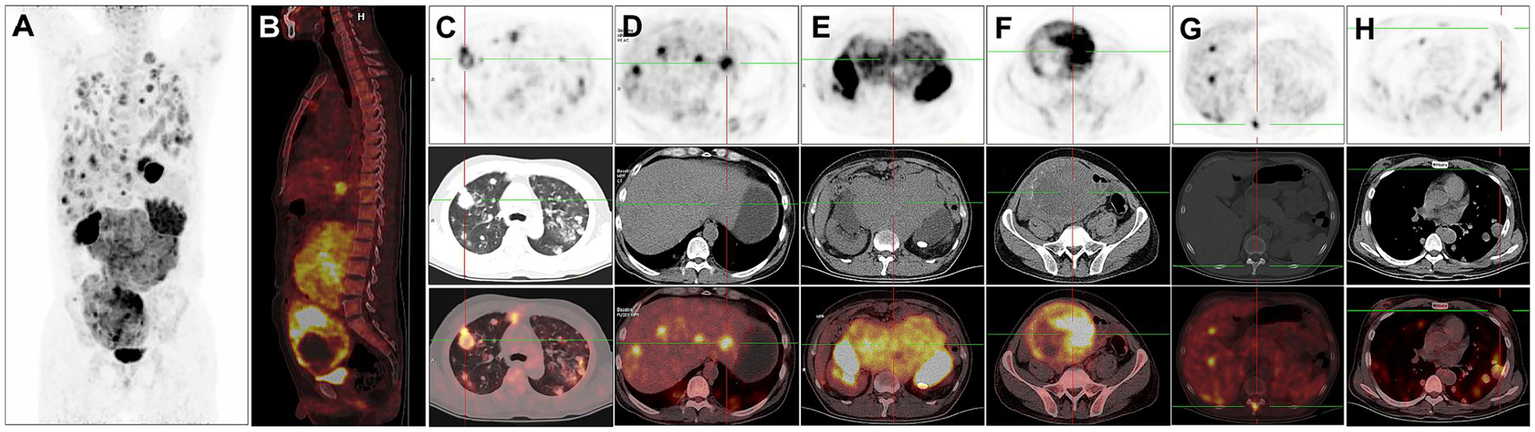

For staging, the patient underwent further 18F-FDG PET/CT (Figures 2A,B). The 18F-FDG PET/CT scan, performed utilizing Siemens Biograph Truepoint 64 PET/CT machine, was conducted 60 min after the intravenous administration of 18F-FDG (6.1 mCi), revealing multiple soft tissue nodules in both lungs with significantly increased 18F-FDG uptake (SUVmax = 12.7, Figure 2C). The liver exhibited multiple slightly hypodense nodules and masses, characterized by markedly increased 18F-FDG uptake (SUVmax = 38.6). The larger liver mass measured approximately 3.6 cm × 2.1 cm (Figure 2D). In the retroperitoneum, numerous intermingled soft tissue masses with markedly increased 18F-FDG uptake (SUVmax = 13.1) were observed, with the largest dimension measuring about 16.2 cm × 16.3 cm. Additionally, patchy calcifications were evident within this area (Figure 2E). A soft tissue mass of irregular shape was identified in the right pelvis, displaying unevenly increased 18F-FDG uptake (SUVmax = 19.5). The maximum dimensions of this mass were approximately 12.0 cm × 15.2 cm, with areas of cystic necrosis and calcifications noted (Figure 2F). Markedly increased 18F-FDG uptake (SUVmax = 11.8) was detected at the thoracic 11 vertebral attachments (Figure 2G). Notably, no testes were visualized in the bilateral scrotum. The bilateral breast glands exhibited thickening with a slight increase in 18F-FDG uptake (SUVmax = 1.2, Figure 2H).

Figure 2

18F-FDG PET/CT images of male choriocarcinoma with multiple systemic metastases (December 20, 2018). (A) The anteroposterior 3-dimensional maximum intensity projection (MIP) image demonstrates increased metabolic activity in the both lungs, abdominal cavity, and pelvic cavity. (B) The sagittal fusion image demonstrates increased metabolic activity in the liver, retroperitoneum and pelvis. (C) Transverse images reveal multiple soft tissue nodules in both lungs with significantly increased 18F-FDG uptake (SUVmax = 12.7). (D) Transverse images reveal the liver exhibiting multiple slightly hypodense nodules and masses, characterized by markedly increased 18F-FDG uptake (SUVmax = 38.6). (E) Transverse images depict, in the retroperitoneum, numerous intermingled soft tissue masses with markedly increased 18F-FDG uptake (SUVmax = 13.1). (F) Transverse images identify a soft tissue mass of irregular shape in the right pelvis, displaying unevenly increased 18F-FDG uptake (SUVmax = 19.5). The maximum dimensions of this mass are approximately 12.0 cm × 15.2 cm, with areas of cystic necrosis and calcifications noted. (G) Transverse images reveal markedly increased 18F-FDG uptake at the thoracic 11 vertebral attachments (SUVmax = 11.8). (H) Transverse images show the bilateral breast glands exhibiting thickening with a slight increase in 18F-FDG uptake (SUVmax = 1.2).